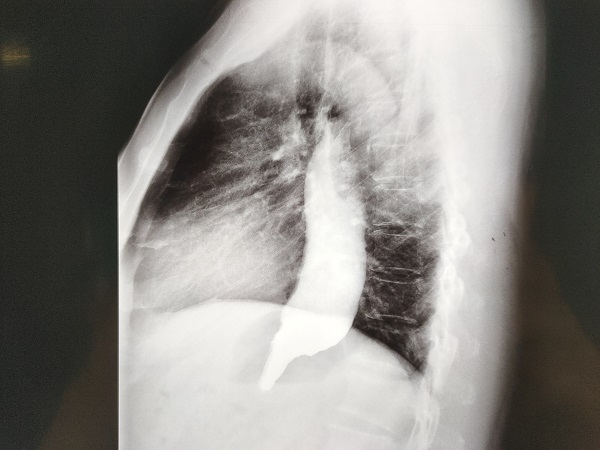

11月16日D2B(D2W)时间仅16分钟!创造了我院抢救急性心肌梗死新的记录!图片来源:网络“胸痛病人转贵院,已服“心梗一包药”并术前谈话同意手术。”宜春学院第一附属医院 万载县人民医院心血管科涂小明主任正在总查房,突然收到胸痛中心远程会诊提示,原来是经过胸痛中心培训的黄茅镇卫生院医生首诊之后已完成了心电图检查并确诊了急性心肌梗死,然后发出了远程胸痛病人预警,涂小明主任根据心电图结果再次确诊后立即启动介入...